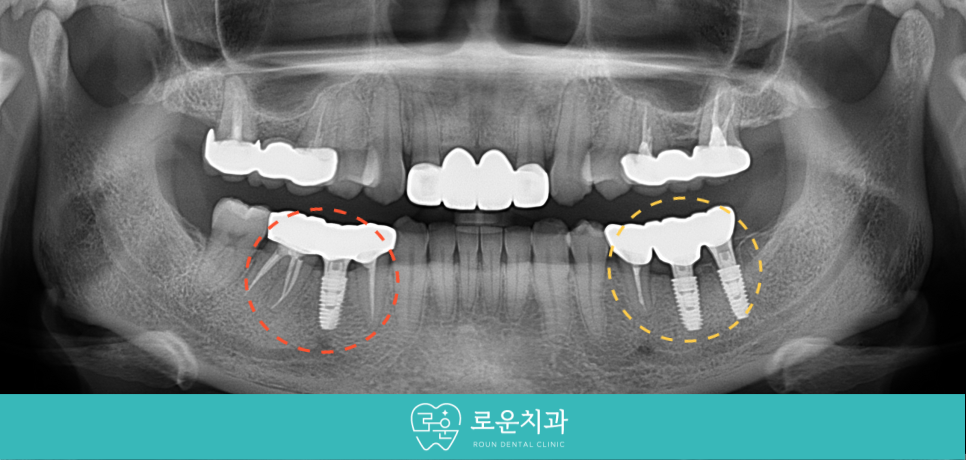

오늘은 아래턱 왼쪽 아래

기존 브릿지 보철물 부위의 심한 통증으로 인해

로운치과를 내원해 주신 환자분의 사례를

소개해 드리겠습니다.

오늘 소개해 드릴 환자분께서는 30대 여성분으로

아래턱 왼쪽 아래 과거 보철물을 수복했던 부위에서

통증과 흔들림이 느껴지신다며

검사와 치료를 위해 찾아주셨습니다.

먼저 구강 내에서

확인해 보았더니

아래턱 왼쪽 어금니 부위

기존 브릿지 보철물의 맨 뒤의 치아에서

심한 동요도가 있었는데요.

정밀한 검사를 위해

파노라마 사진을 촬영해 보았더니

두 지대치 모두 뿌리 끝 염증이 있었지만

특히 맨 뒤의 두 번째 큰 어금니(#37)가

더 심하였으며 동요도까지 있었는데요.

용호동임플란트 로운치과에서는

가급적 자연치아를 살릴 수 있는 방향으로

꼼꼼하게 검사를 진행한 결과

아래턱 왼쪽 두 번째 작은 어금니(#35)는

보철물 제거 후 재 신경치료를 통해

단독으로 크라운 수복을 도와드리기로 하였으며,

두 번째 큰 어금니(#37)는

발치 후 바로 앞의 상실 부위와 함께

용호동임플란트 식립을 도와드리기로

치료 계획을 수립하였습니다.

그동안 상실된 부위의 용호동임플란트를

먼저 식립을 도와드렸는데요.

파노라마 사진과 3D CT 촬영을 통해

잔존 치조골의 양과 두께,

눈에 보이지 않는 해부학적 구조물,

아래턱 하방으로 지나가는

하치조 신경관의 위치 등을 면밀하게 확인한 뒤

정확한 위치와 방향으로

임플란트 식립을 도와드렸습니다.

식립 후 임플란트가

주변 잇몸뼈와 단단히 결합되었을 때

양옆의 크라운 보철물과 같은

지르코니아로 최종 보철물 제작을 도와드리면서

치료를 마무리해 드렸습니다.

[치료 전 -> 후]